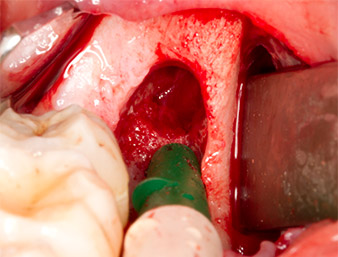

To obtain autogenous material for subsequent wound treatment, healthy bone chips were harvested from the surroundings of the root remnant with a piezo surgical instrument (Piezomed B5) (Fig. 5).

Piezomed B5

Fig. 5: Bone in the region of the alveole is lifted with a chisel-shaped piezo surgical instrument (Piezomed B5). This bone is used as autologous augmentation material after removal of the root remnant (cf. Fig. 13 and 14).

The autogenous tissue was removed with the scraper-shaped section of the working part of the instrument and stored in a physiological saline solution until further use (cf. Fig. 13).